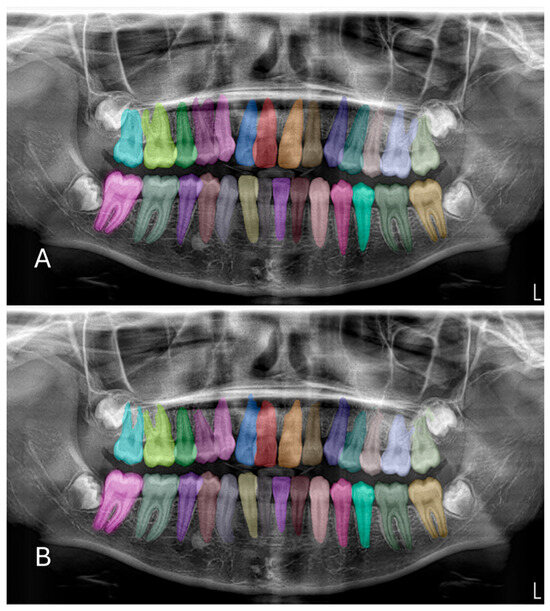

Artificial Intelligence-Based Evaluation of Permanent First Molar Extraction Indications in Children Using Panoramic Radiographs

Background: The aim of this study was to develop an artificial intelligence (AI)-based decision support model for evaluating the extraction indication of permanent first molars in pediatric patients using panoramic radiographs, and to investigate the potential contribution of this model to the clinical decision-making process. Methods: This retrospective observational study analyzed 1000 panoramic radiographs obtained from children aged 8–10 years who attended the Clinics of Batman University Faculty of Dentistry for routine dental examination. Among the radiographs meeting the inclusion criteria, a total of 176 panoramic images were selected based on dental maturation assessment using the Demirjian tooth development staging system. Cases in which the permanent second molar was classified as Demirjian stages E–F were labeled as “extraction indication present”, while the remaining stages were labeled as “extraction indication absent”. A balanced dataset was created, consisting of 88 cases in each group. Image features were extracted using Gabor filters and Histogram of Oriented Gradients (HOG). The selected features were analyzed using a Support Vector Machine (SVM) classifier with a radial basis function (RBF) kernel. Model performance was evaluated using accuracy, sensitivity, specificity, F1-score, and area under the receiver operating characteristic curve (ROC–AUC). Results: The proposed Gabor–HOG–SVM-based AI model achieved an overall classification accuracy of 77.78% with an AUC value of 0.77 in distinguishing between “extraction indication present” and “extraction indication absent” cases. For the extraction-indicated group, the sensitivity was 0.81 and the F1-score was 0.79, whereas for the non-indicated group, the sensitivity and F1-score were 0.74 and 0.77, respectively. No statistically significant differences were observed between the groups in terms of age or sex distribution (p > 0.05). Conclusions: This study demonstrates that artificial intelligence-based analysis of panoramic radiographic images can provide an objective and reproducible decision support approach for evaluating extraction indications of permanent first molars in pediatric patients. The proposed model should be considered as an adjunctive tool to reduce observer-dependent variability rather than a replacement for clinical judgment, and its clinical applicability should be further validated through multicenter and multi-parametric studies. Full article